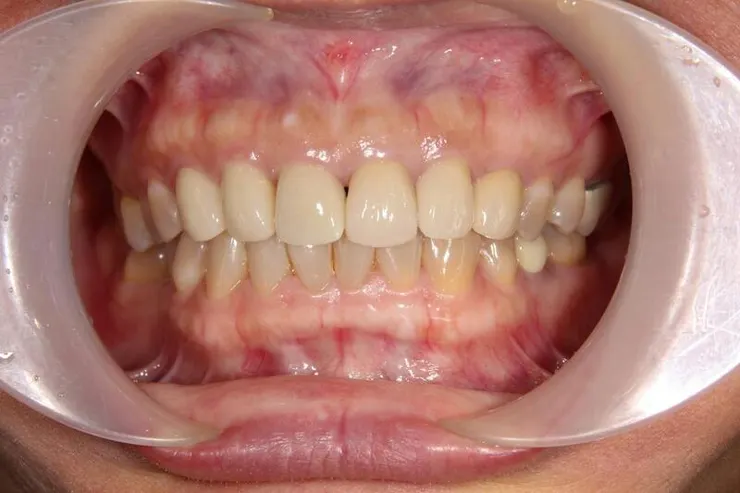

再經過一年,假牙看起來更自然了,當初剛裝假牙時的牙齦,病人自己說大概一個多月就自動長好恢復了

正中門牙的黑三角,無解,那是成人重做門牙或矯正常見的問題,因為已不像年輕人的牙齦那麼有再生活力與適應力,所以很多牙醫師都喜歡做連在一起的假牙,解決黑三角的問題(可參考她最上面的原始假牙),可這是對醫師方便、好,對病人的健康並不好。

這是2021的,一樣自然好看

她有用音波牙刷潔牙,保持牙周健康,牙齦更飽滿了,假牙看起來更自然(可以跟她其他的金屬瓷牙比較)